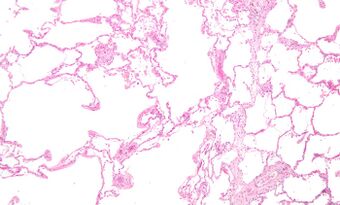

Emphysema low mag.jpg

Micrograph of an emphysematous lung; emphysema is a rare respiratory disease, strongly associated with smoking. H&E stain.